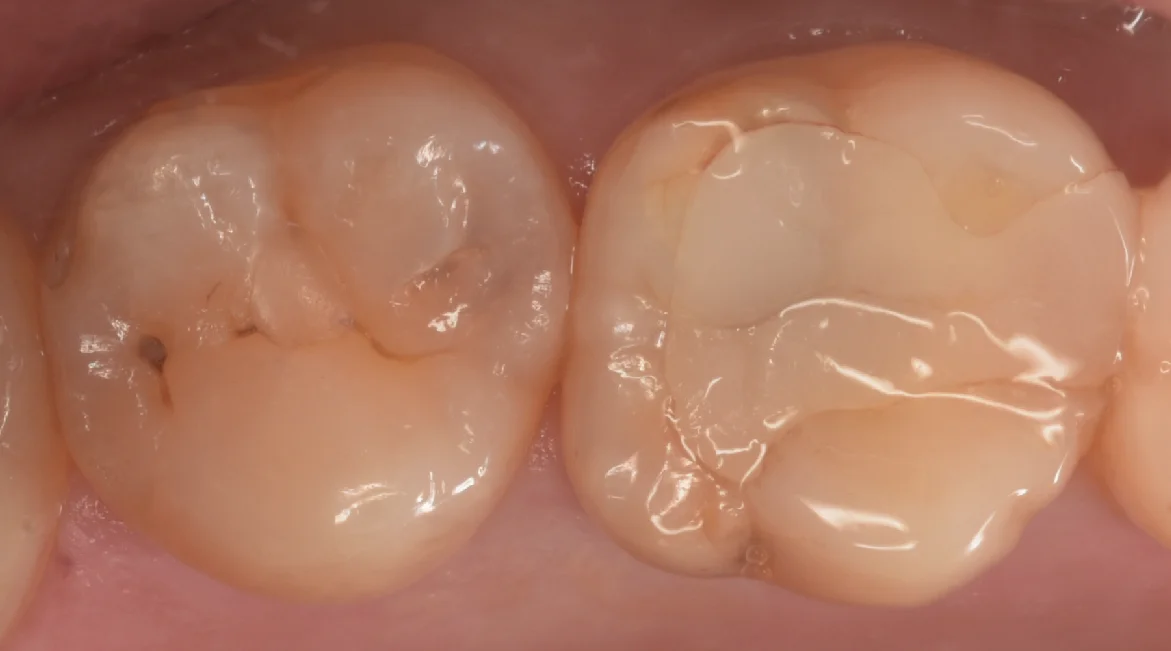

まずは術前からです。

写真左側の歯を治療しました。

中心に小さく保険のCRを行なっており、手前の歯の間側・後ろの歯の間の小さな穴にそれぞれ虫歯があります。